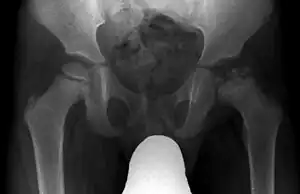

X-rays of the hip may suggest or verify the diagnosis. X-rays usually demonstrate a flattened, and later fragmented femoral head. A bone scan or MRI may be useful in making the diagnosis in those cases where X-rays are inconclusive. Usually, plain radiographic changes are delayed six weeks or more from the clinical onset, so bone scintigraphy and MRI are done for early diagnosis. MRI results are more accurate, i.e., 97 to 99% against 88 to 93% in plain radiography. If MRI or bone scans are necessary, a positive diagnosis relies upon patchy areas of vascularity to the capital femoral epiphysis (the developing femoral head).